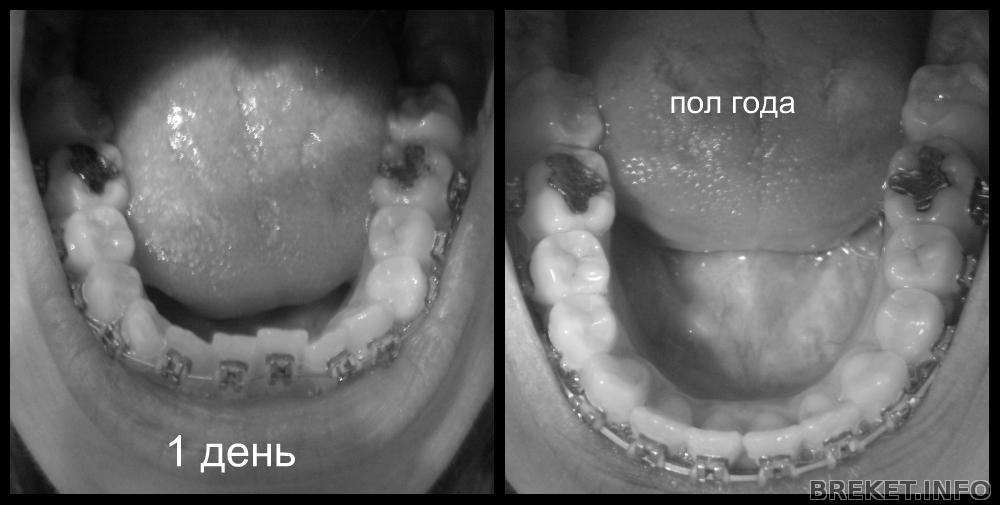

Вот такие результаты:

9 месяцев.jpg

9_vtczwtd.jpg

пол года.jpg